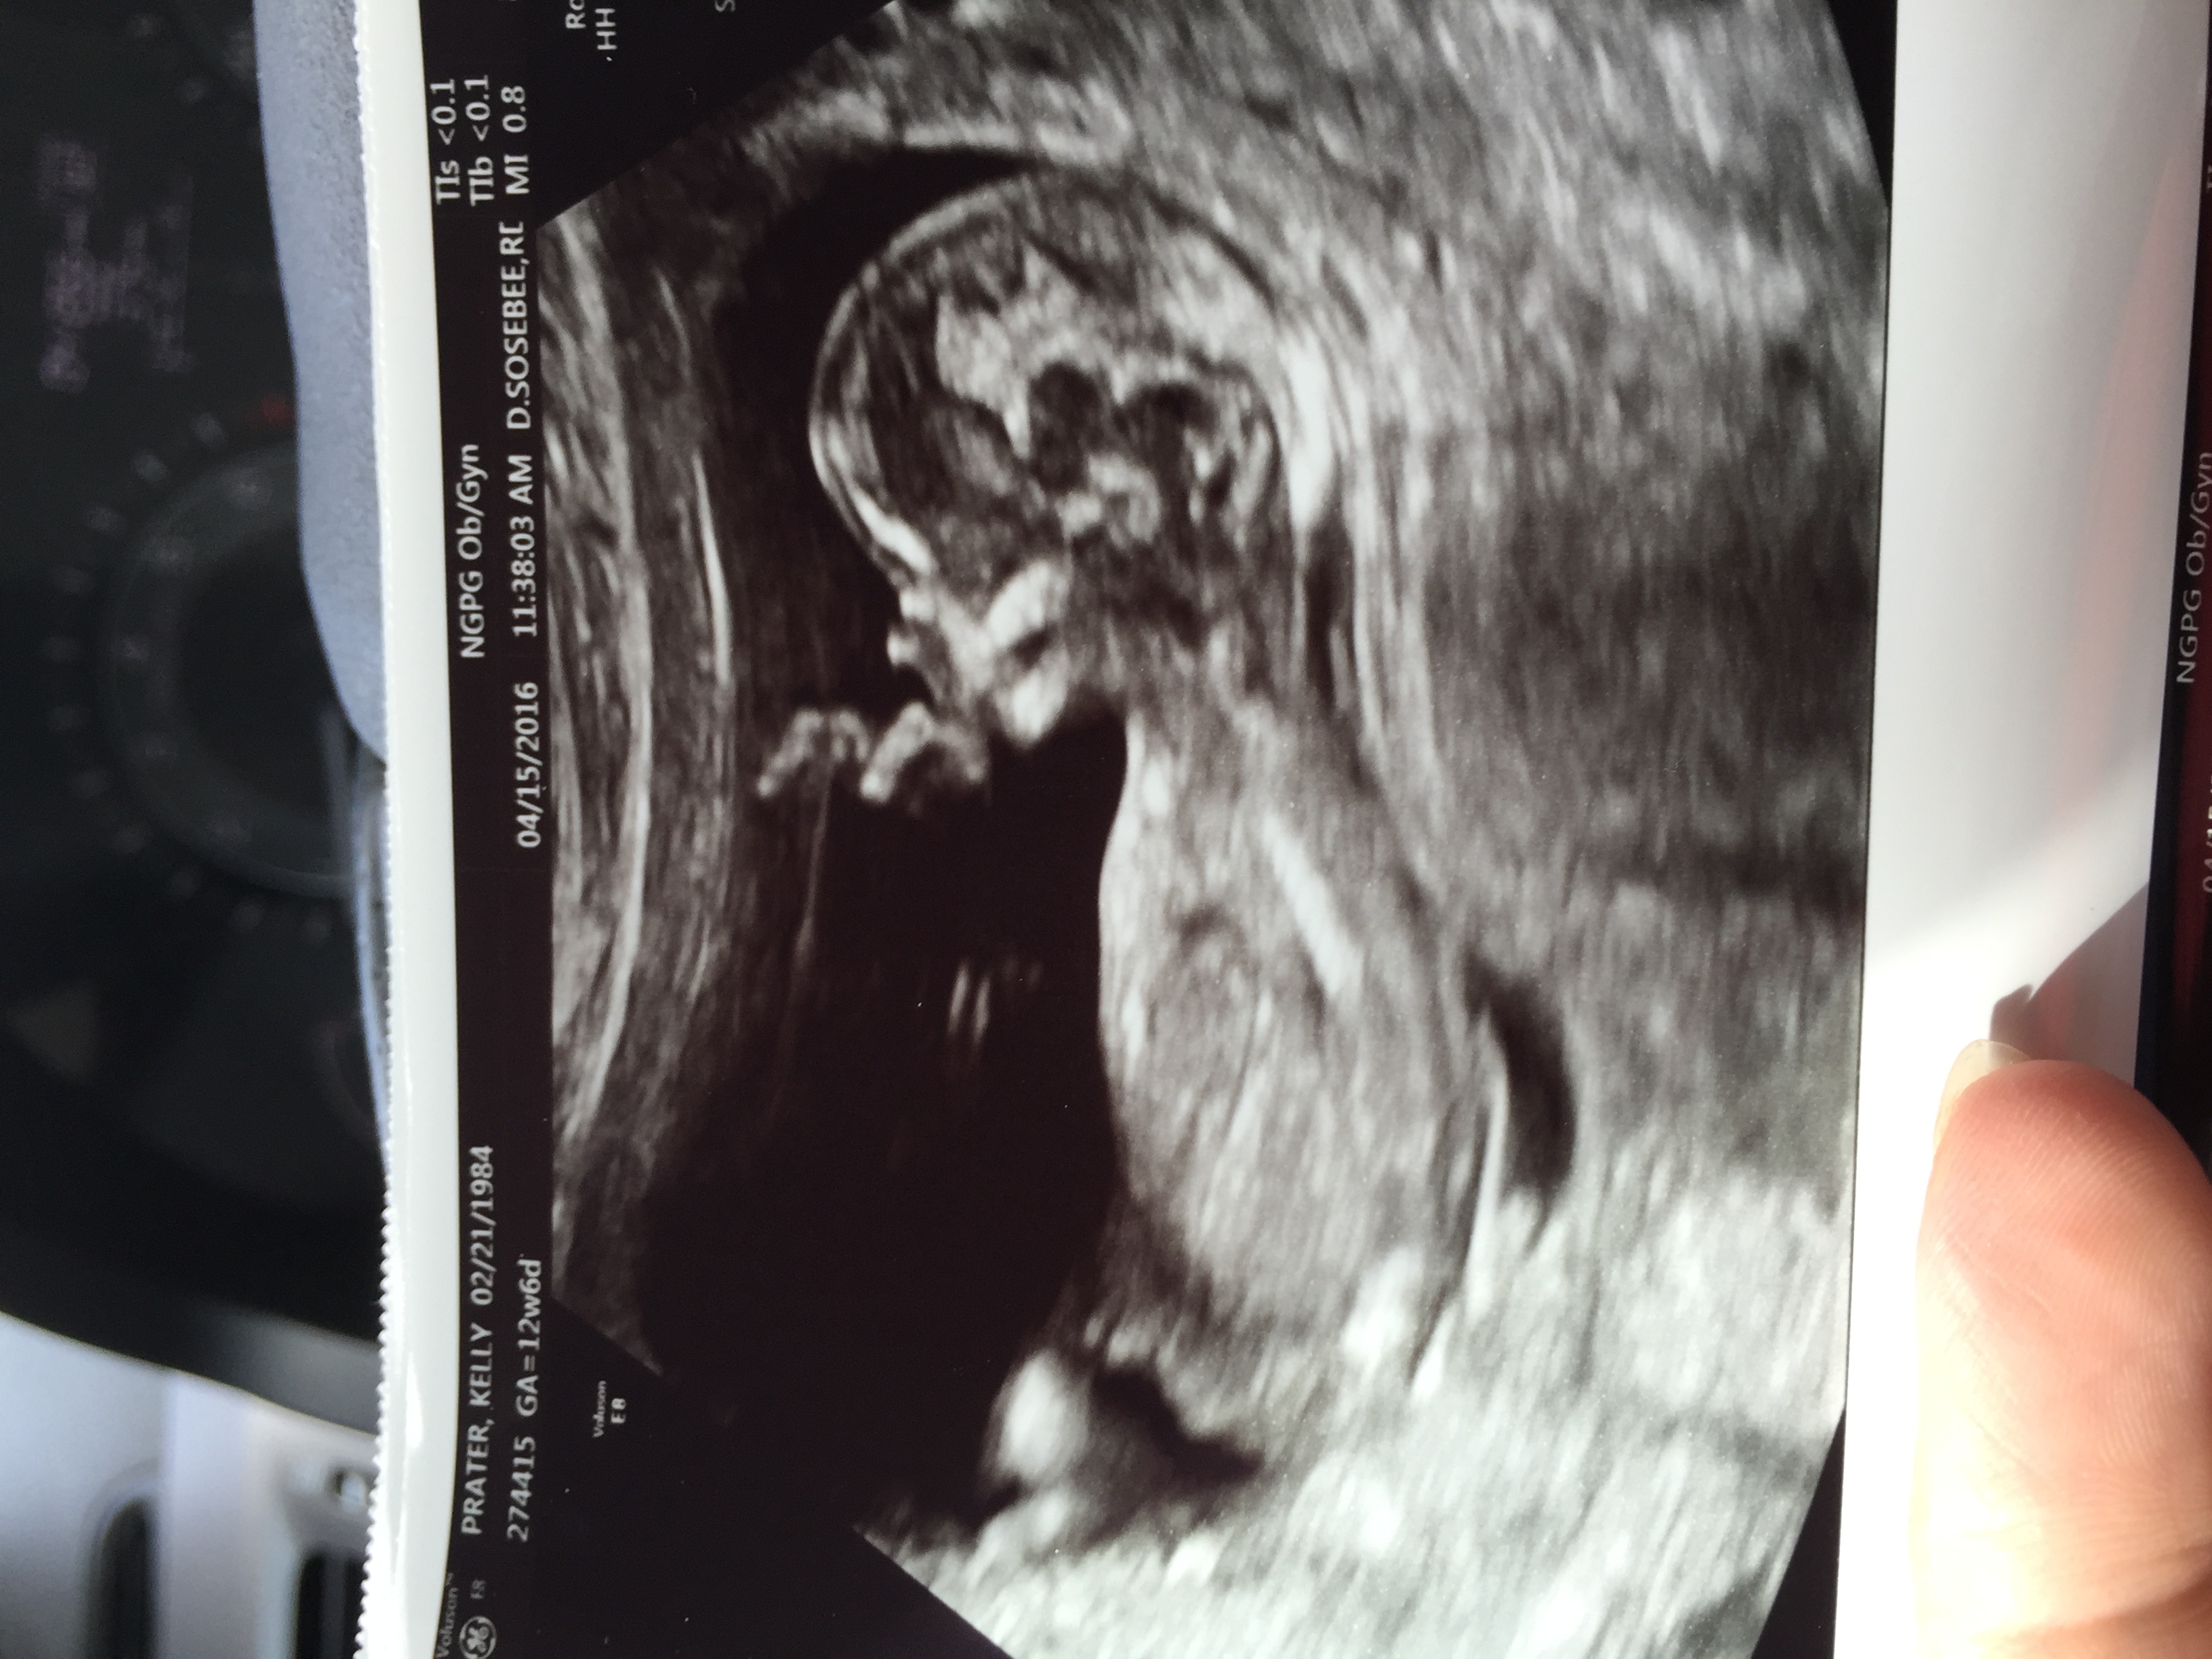

Any guesses? Bc we could not see anything tech thinks girl? This will be our 4th girl. Attachment 30844Attachment 30845

I can't really make out that first shot but I think 13 weeks is too early for a potty shot. I thought I read somewhere that what looks like a girl, can easily be a boy later on as parts develop. I'm no good at nub guesses so I really have no idea here but I just wanted to mention that.

If what I'm seeing in the 2nd picture is a nub, leaning girl

Too early for potty shot, nub on side shot looks a little pink but I would not hang my hat on that. Still early